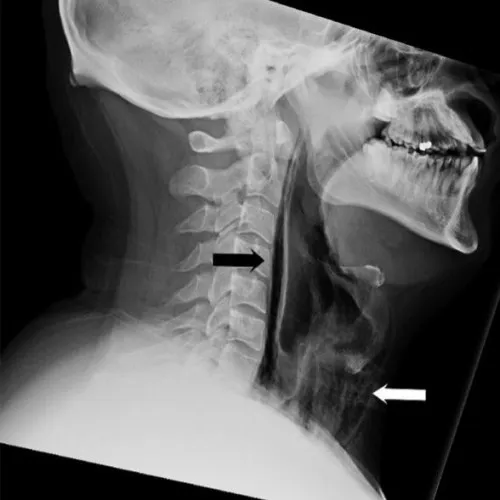

Khi thăm khám, các bác sĩ nghe thấy tiếng lộp bộp cùng vài tiếng gãy vỡ kéo dài từ cổ đến xương sườn bệnh nhân. Đây là dấu hiệu các bong bóng khí đã chạm đến mô và cơ sâu trong ngực. Ảnh chụp cắt lớp sau đó đã xác nhận điều này.